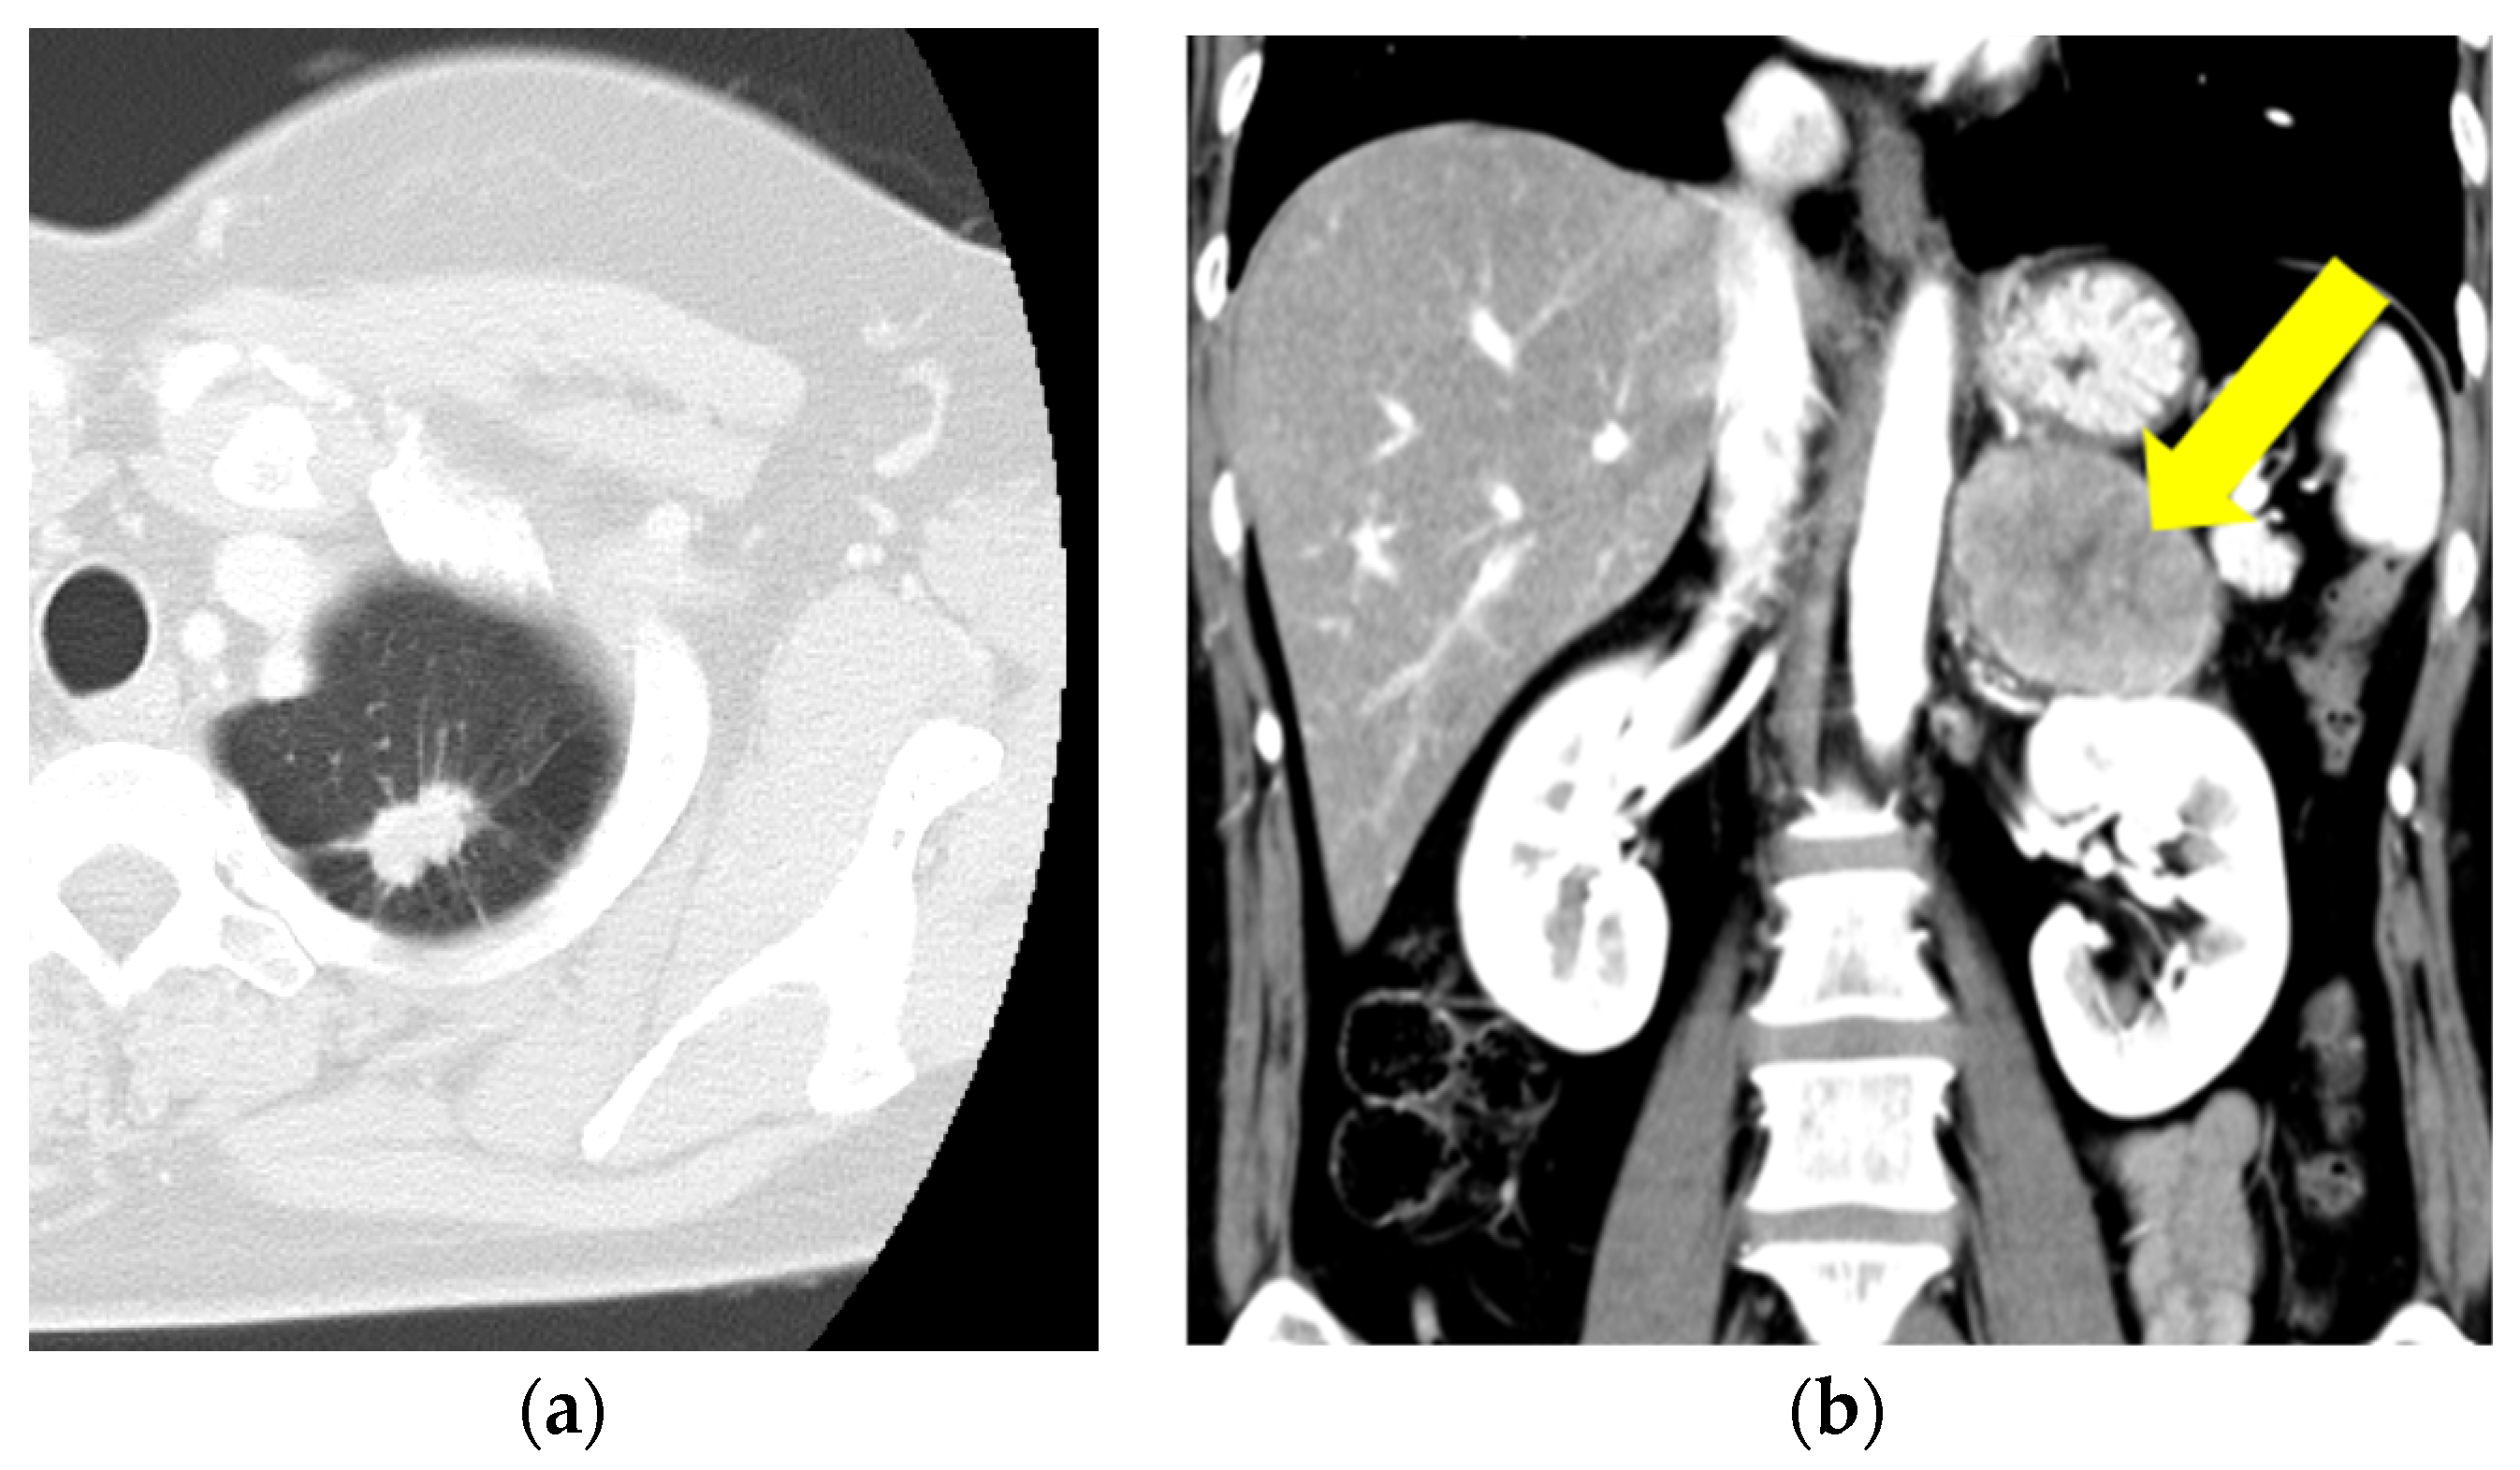

A 51-year-old Japanese woman was diagnosed with stage IV lung adenocarcinoma with adrenal metastasis based on the results of computed tomography and biopsies of both tumors (Figure 1a,b).

Figure 1. (a,b) Computed tomography reveals lung adenocarcinoma (a) and adrenal metastasis (b) (yellow arrow).